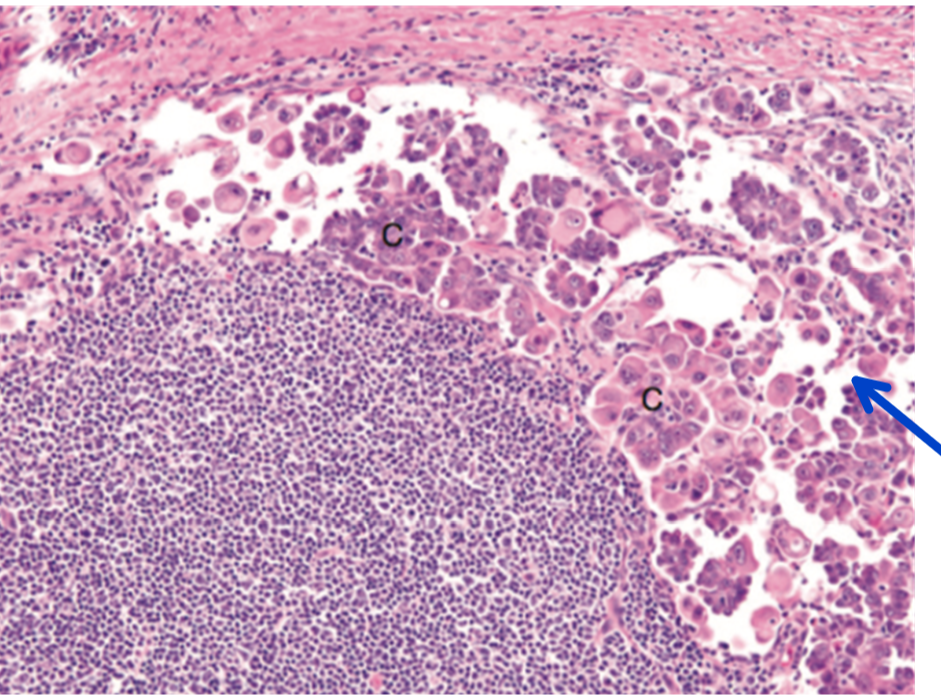

Q

This is from the eyelid and ocular bone, provide a histologic morphologic diagnosis. (Note: there is metastasis to the lung)

A

ocular squamous cell carcinoma with local bone invasion and pulmonary metastasis

How well did you know this?

Trace the probable route of metastasis from the primary site in the eye to the secondary metastatic sites in the lung.

Lymphatic invasion is likely, which would mean invasion by single or clumps of neoplastic squamous cells into the lymphatic vessels within and surrounding the eye. Arrest of these cells in local lymph nodes and regional chains (parotid, retropharyngeal, cervical chain) and progressive movement with the lymph flow to empty into the right lymphatic duct, the thoracic duct, or directly into the vena cava near the thoracic inlet. The neoplastic cells then become blood borne and flow through the cranial vena cava, right atrium, right ventricle, pulmonary arteries and lodge in the small pulmonary arteries and capillaries where clusters of cells may take hold and set up secondary sites.